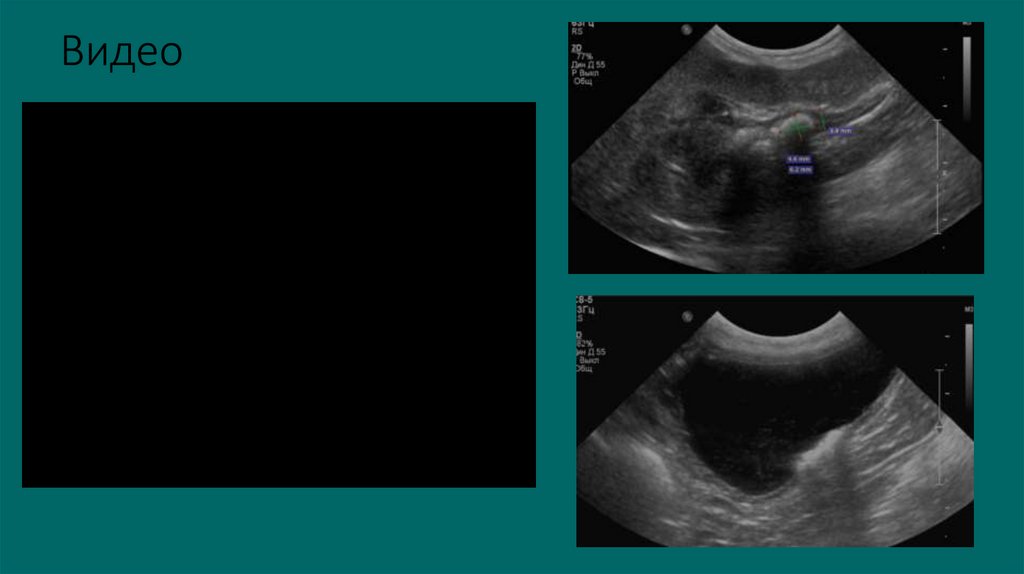

Видео